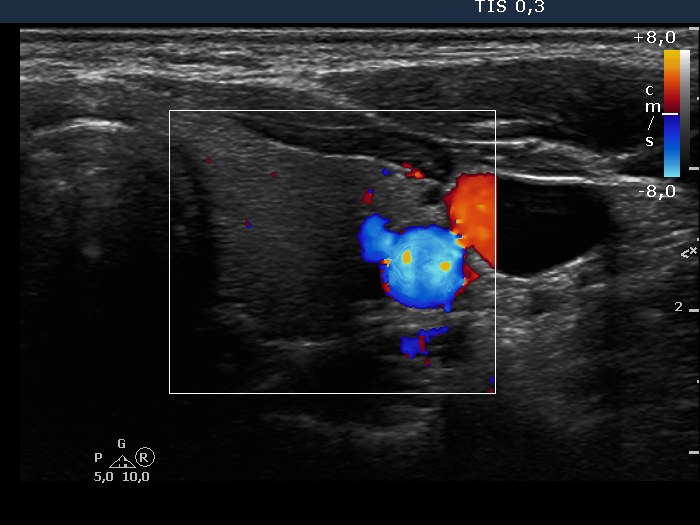

Ultrasonography: the thyroids were intact, i.e. the basic echo structure was echonormal and only a few small hypoechogenic areas were found. The echogenicity index was less than 1%. The vascularization was not specific.